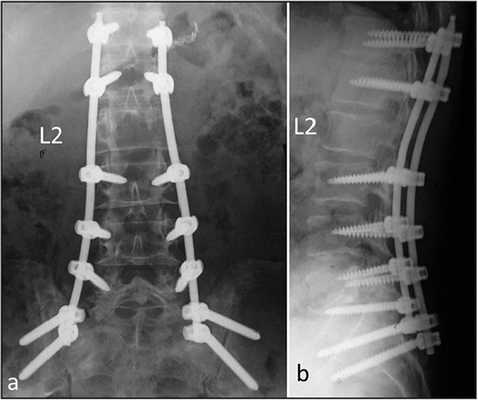

Стабилизационная система на рентгене.

В большинстве случаев проблемный сегмент стабилизируют с помощью металлоконструкций, чаще представленных транспедикулярными системами и пластинами с винтами из высокотехнологичных сплавов металла. В хирургии такая техника называется инструментацией позвоночника. Кроме металлоконструкций, для стабилизации также могут быть применены полимерные устройства, сделанные, например, из углеводородного волокна или резорбирующегося высокомолекулярного биополимера. К отдельной разновидности стабилизирующих вмешательств, которые не причисляют к инструментации, относят установку кейджей имплантатов межпозвоночных дисков.

Системы стабилизации позвоночника жесткого типа

Жесткие, или неподвижные металлоконструкции подразумевают закрепление позвонков в постоянном фиксированном положении. Устанавливаются они из заднего доступа (со стороны спины) под контролем КТ и рентген-аппаратуры. Крепятся к позвонкам резьбовыми винтами, которые погружают в костные тела на глубину до 80%. Рекомендуют ставить подобного плана системы сугубо в безальтернативных случаях, если ни один другой вид лечения не сможет решить проблему с поврежденным отделом позвоночника.

Стабилизация поясничного отдела.